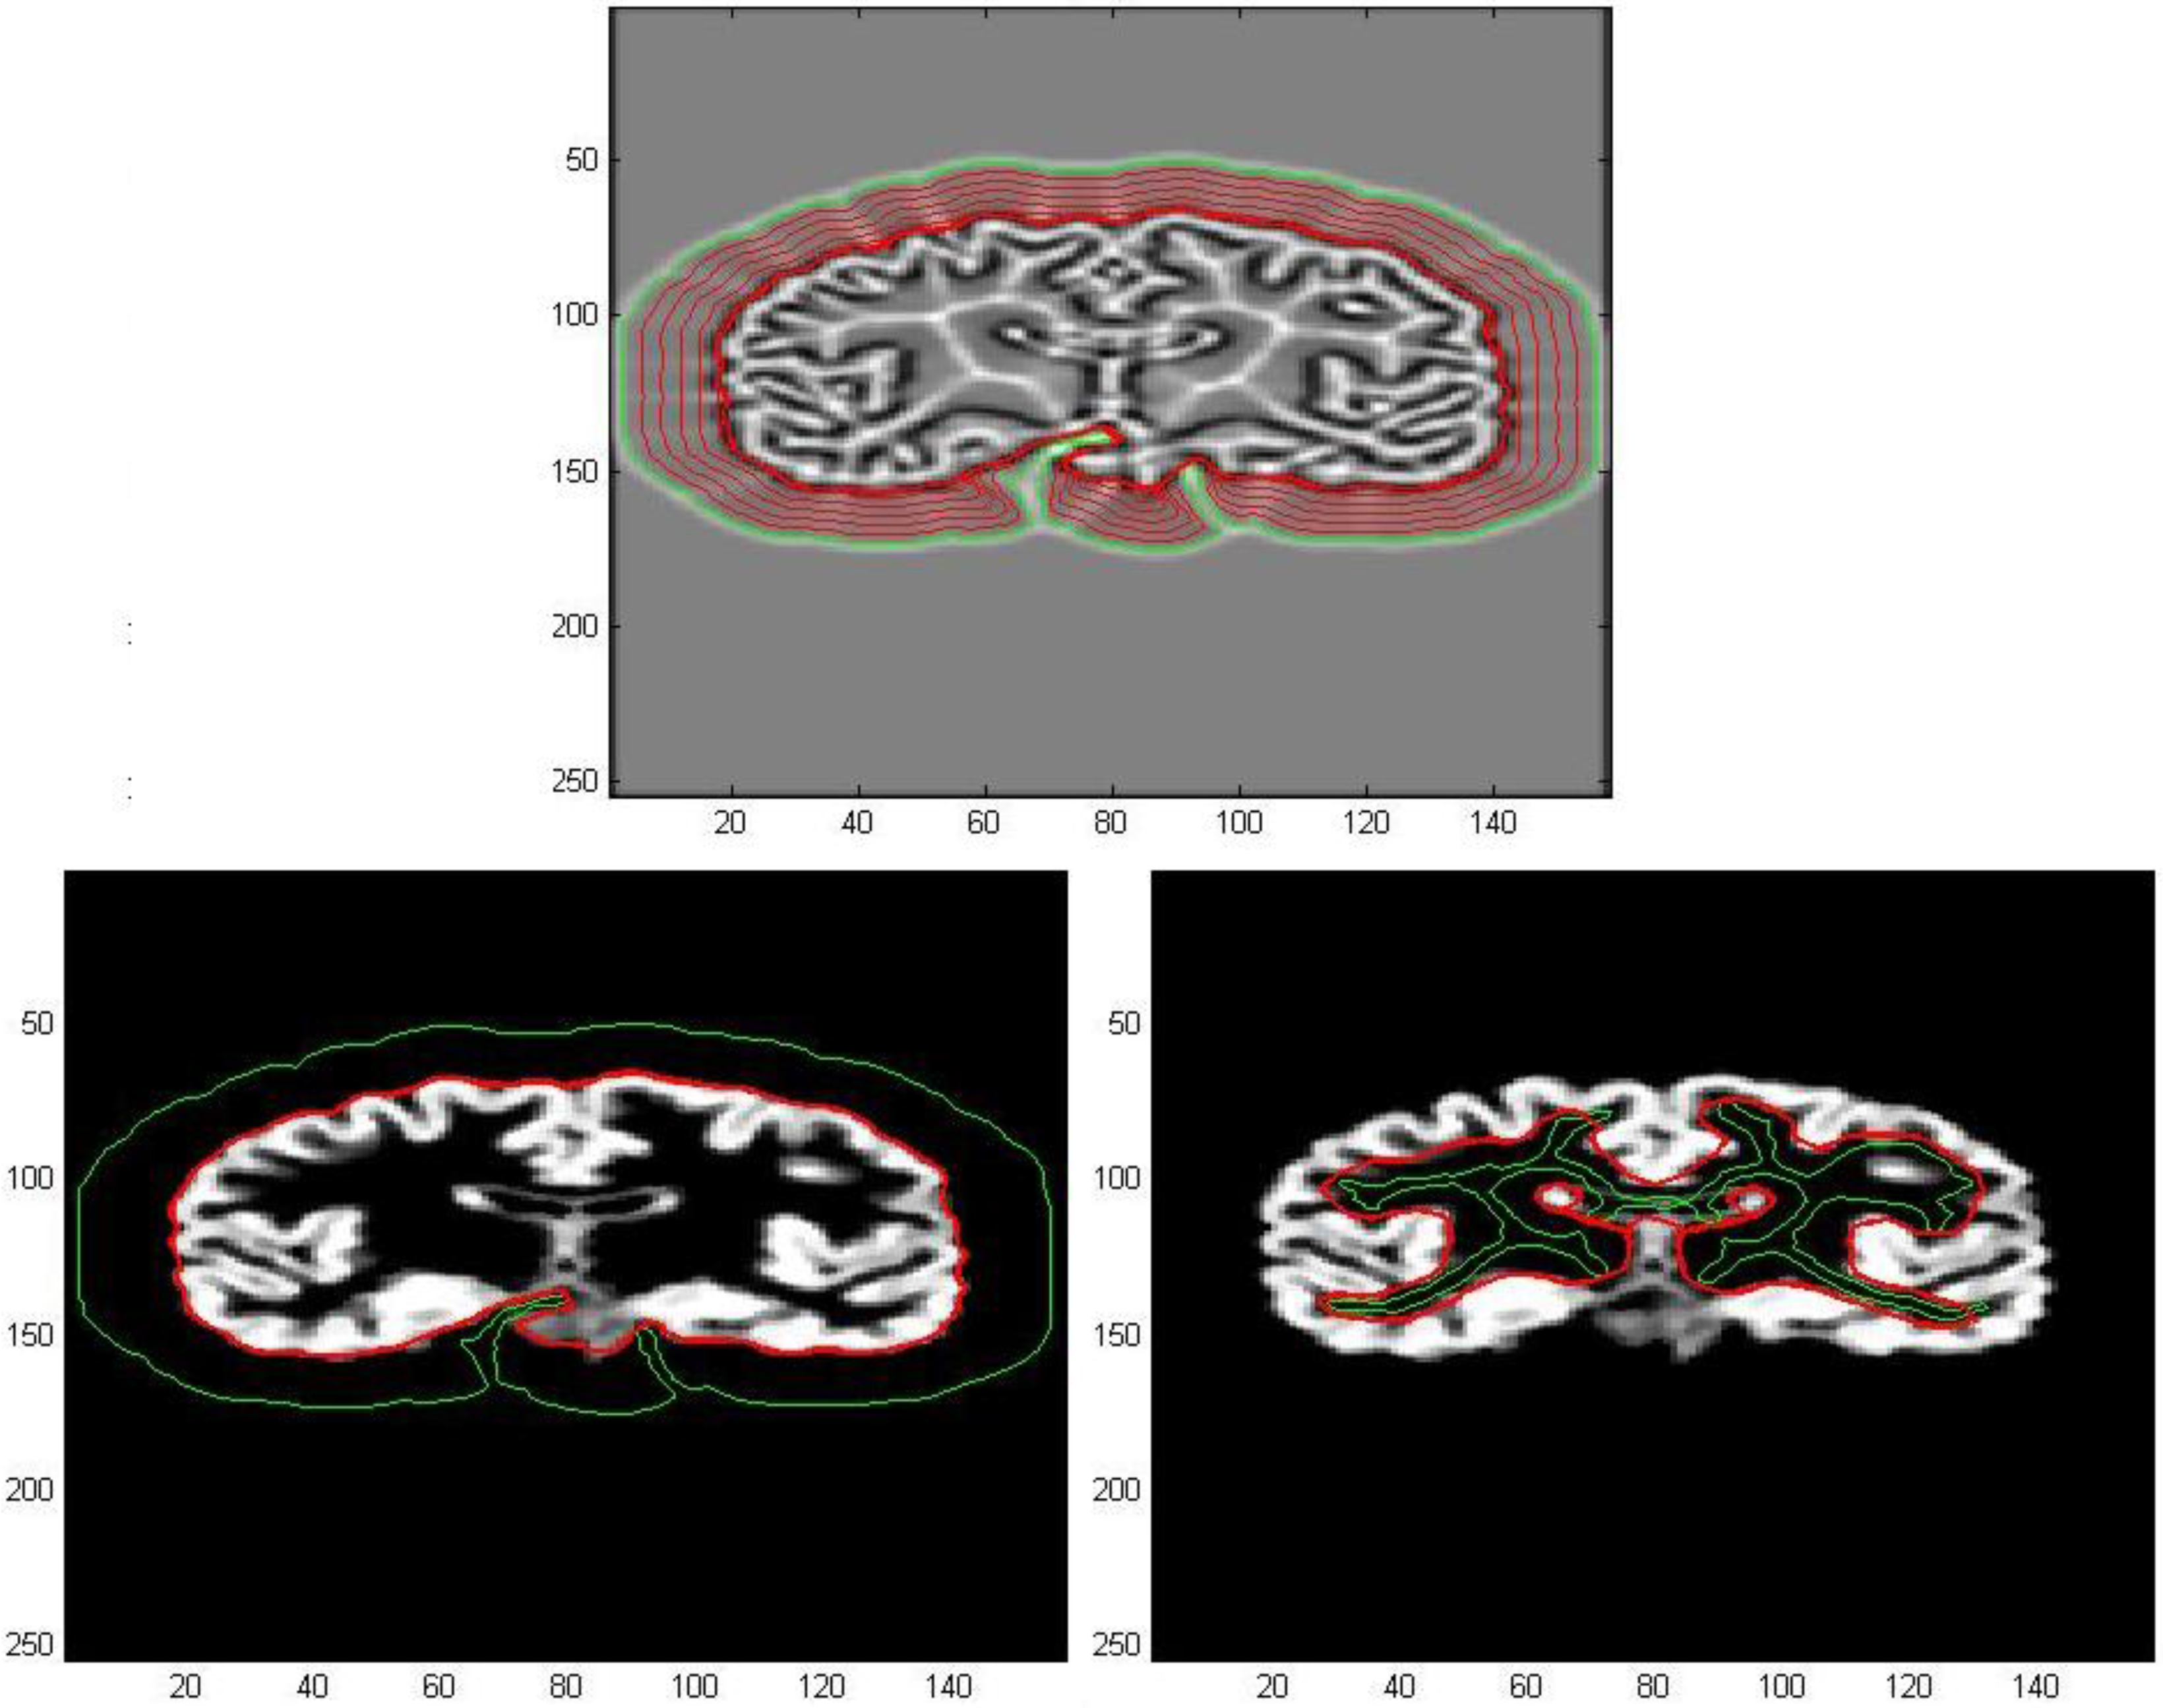

The vector field so determined, from now on called AVF field, will be used for image processing in the subsequent applications. In Figure 7a,b, we could compare the AVF field derived from Equation (8) with GGVF field obtained through Equation (7), for the same number of iterations. This model could provide us an extension of the capture range, specifically an enlargement of areas inside which any initial contour may be placed. These regions result as well defined in the divergence map because it is delimited by curves corresponding to opposite values of divergence. As a consequence, we have a complete characterization of the capture range for a vector field that will be of great help in snake initialization procedures.

Figure 7. (a) Divergence map of AVF Field; (b) Divergence map of GGVF field after 100 iterations after 100 iterations.

Algorithms 05 00636 g007

These areas are varying according to the number of iterations after which the flow process has been interrupted in the numerical resolution of both Equations (7) and (8). Consequently, the evaluation of the AVF vector field will be less time consuming compared to the GGVF because we could choose a reduced number of iterations in order to have a comparable capture range size and to achieve similar results. Moreover, by increasing the number of iterations, the sides of areas that delimit parts of image inside which the field is null, collapse each other, especially in conjunction with deep and narrow concavities, as can be seen in Figure 8b. Therefore, the curves of high divergence allow us to clearly identify those parts of detected edges with high curvatures that result to be the most significant from the geometrical and morphological point of view.

Figure 8. (a) Divergence map of AVF field; (b) Divergence map of AVF field after 60 iterations after 180 iterations.

Algorithms 05 00636 g008